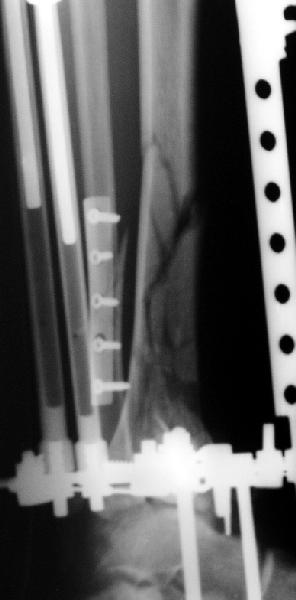

Вот что получилось

7.jpg

27KB (28411 bytes)

Пластинка красивая. Чуть только спереди назад идет, не сосем по оси большеберцовой кости. А там не маловато фиксаторов собственно в дистальном суставном конце кости? А вправляли его как? Как будто или осталось запрокидывание кзади или недонизведен передний край. Но с учетом исходного тяжелейшего повреждения - все равно здорово.